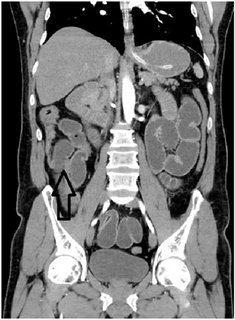

La tomografía de abdomen total simple y contrastada reportó “Vesícula biliar no visualizada, en su reemplazo se observan cambios en la densidad del hilio hepático y lecho vesicular, con colecciones de aire. A nivel de la válvula ileocecal reducción importante de calibre, no se observa cuerpo extraño ni masa, tampoco alteraciones de la grasa peri-cecal. Considerar engrosamiento o efecto estenótico parcial a nivel de válvula ileocecal que condiciona obstrucción intestinal (solo intestino delgado). Se observa distensión marcada de todas las asas delgadas desde el duodeno hasta el íleon distal” (Figura 2 y Figura 3).

Figura 3. Tomografía axial computarizada de abdomen con efecto estenótico parcial a nivel de la válvula ileocecal que condiciona obstrucción intestinal.

La Tomografía computarizada (TAC) abdominal, permite evidenciar la ubicación del cálculo y de la obstrucción intestinal8, visualizar neumobilia, neumocolecisto, fístula bilio-entérica, niveles hidroaéreos y liquido libre en cavidad17,18, también permite identificar el tamaño del cálculo11. La tomografía se considera el patrón de oro para el diagnóstico de íleo biliar2 y si se usa contraste arroja una sensibilidad mayor al 90%19. En las imágenes del paciente, la TAC de abdomen mostró aire en el lugar de la vesícula biliar, así como distensión de asas y obstrucción a nivel de la válvula ileocecal, lo cual orientó la sospecha diagnóstica hacia íleo biliar con la consecuente intervención quirúrgica que llevó a la resolución de su obstrucción.